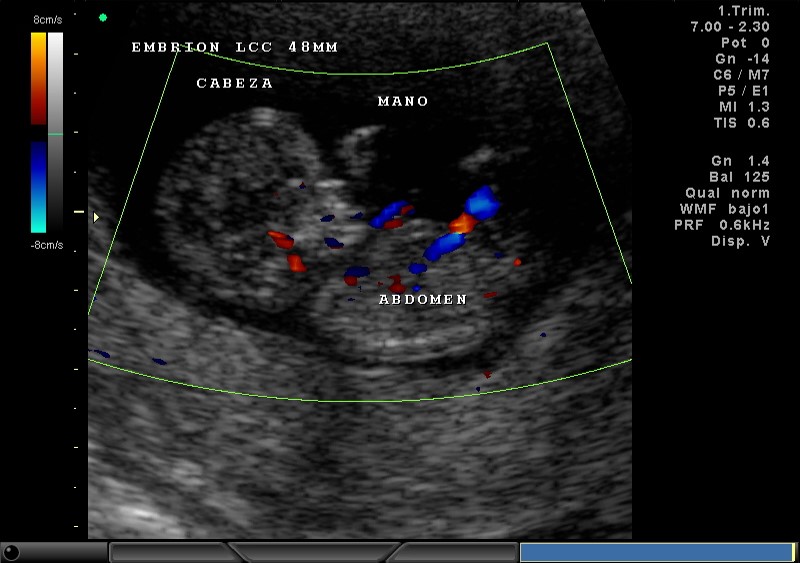

2D Y COLOR PLACENTA, ABDOMEN, CABEZA, MANO 11.5 SEMANAS